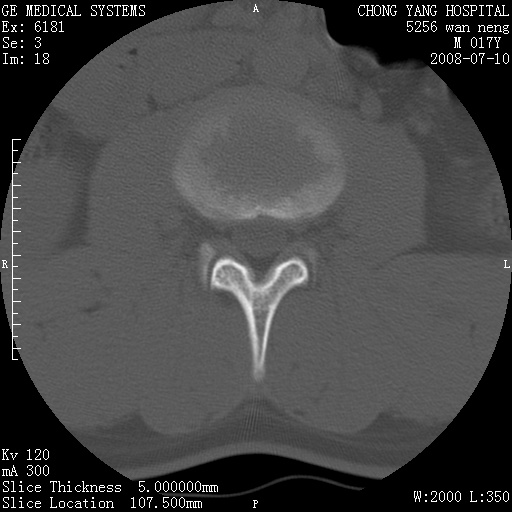

腰3、4椎弓崩裂

腰3、4椎弓不连

支持:腰3、4椎弓峡部崩裂。

腰3、4椎弓峡部不连

支持:腰3、4椎弓峡部崩解。

腰3、4,如受过外伤则为陈旧骨折,否则为骨质不连

图片漂亮,目前也只能看到腰3、4骨质不连

腰3、4椎弓峡部裂。

腰3、4椎弓峡部裂。支持

重建图像见多个椎弓峡部不连(不足为据),平扫未见异常。

支持腰3、4椎弓峡部崩裂。